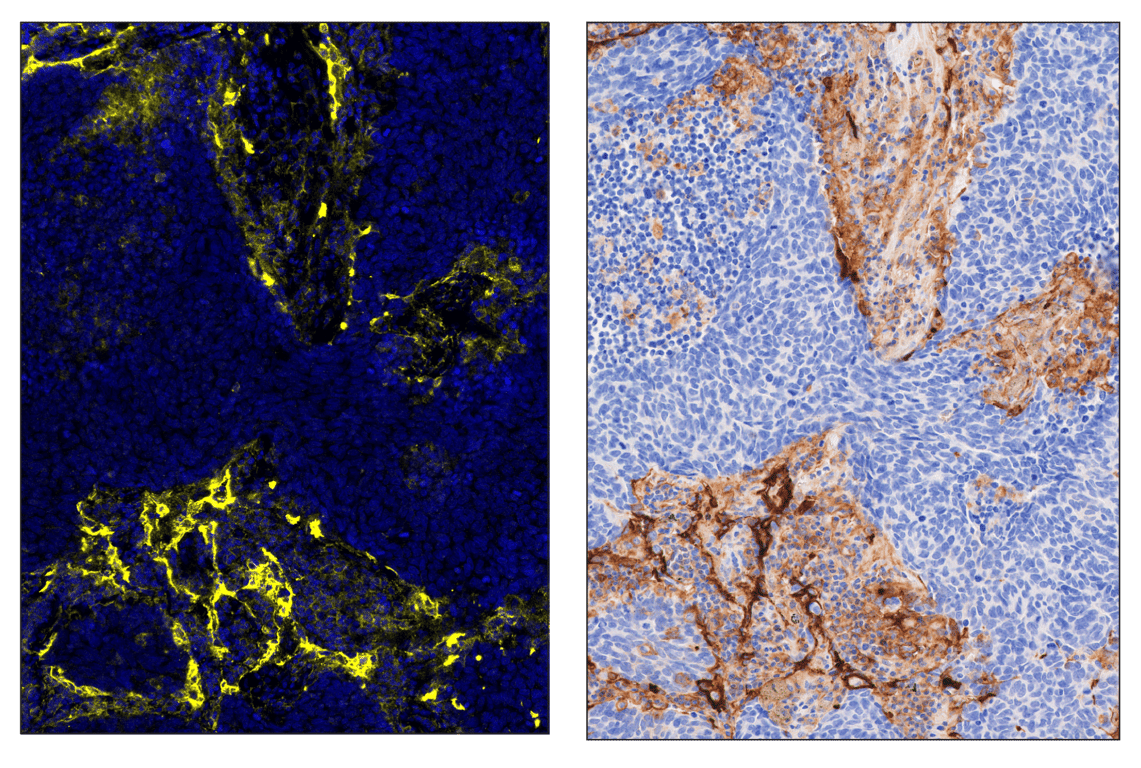

SignalStar multiplex immunohistochemistry (mIHC) is a tool that employs antibodies, oligonucleotides (oligos), and fluorophores to interrogate the cellular presence, location, function, and biomarker co-expression patterns. SignalStar technology enables the detection of multiple phenotypic and functional targets while maintaining spatial context and tissue architecture. These insights are essential for understanding how cells organize and interact to influence the tissue microenvironment and drive disease progression and response to therapy.

The power of the SignalStar system lies in the design of the SignalStar antibodies. These antibodies have been rigorously validated for use in formalin-fixed, paraffin-embedded (FFPE) tissues, and subsequently conjugated to unique oligo tags using site-specific conjugation and thorough purification methodologies. Using a highly specific network of complementary oligos and fluorophores, scientists can amplify the signal for 3-8 targets, even if they are in low abundance.

Figure 1. All antibodies in your plex size of choice (3-8 maximum unique oligo-conjugated antibodies) are added in cocktail in one primary incubation step. Complementary oligos with fluorescent dyes (channels: 488, 594, 647, and 750) amplify the signal of up to 4 oligo-conjugated antibodies in the first round of imaging by building oligo-fluorophore constructs attached to the antibody. If the plex size is greater than 4, the first round of oligos and fluorophores are gently removed, and a second round of amplification is performed to visualize up to 4 additional oligo-conjugated antibodies; the complementary oligo system and the use of the fluorophore removal process enables a second round of antibodies to be amplified from the same substrate, without cross-reactivity. The 2 images are then aligned and fused computationally with either proprietary or open-source software to generate an image consisting of up to 8 targets.

When comparing my SignalStar staining to the chromogenic staining on serial sections, I see more positive cells. How do I know if this excess staining is correct?

During the course of optimization, we've found that fluorescent staining may show higher %-positivity than chromogenic staining. To ensure any excess staining is specific, confirm that the correct subcellular localization and co-localization with other stains are demonstrated. For example, if all CD8+ cells are CD3+, any excess CD8+ staining compared to the chromogenic is most likely correct.

SignalStar™ Multiplex Immunohistochemistry (mIHC) is a technology that employs antibodies, oligonucleotides (oligos), and fluorophores to interrogate cellular presence, location, function, and biomarker co-expression patterns. SignalStar technology enables the detection of multiple phenotypic and functional targets while maintaining spatial context and tissue architecture. These insights are essential for understanding how cells organize and interact to influence the tissue microenvironment and drive disease progression and response to therapy.

The power of the SignalStar system lies in the design of the SignalStar antibodies. These antibodies have been rigorously validated for use in formalin-fixed, paraffin-embedded (FFPE) tissues, and subsequently conjugated to unique oligo tags using site-specific conjugation and thorough purification methodologies. Using a highly specific network of complementary oligos and fluorophores, scientists can amplify the signal for 3-8 targets, even if they are in low abundance.

Figure 1. All antibodies in your plex size of choice (3-8 maximum unique oligo-conjugated antibodies) are added in cocktail in one primary incubation step. Complementary oligos with fluorescent dyes (channels: 488, 594, 647, and 750) amplify the signal of up to 4 oligo-conjugated antibodies in the first round of imaging by building oligo-fluorophore constructs attached to the antibody. If the plex size is greater than 4, the first round of oligos and fluorophores are gently removed, and a second round of amplification is performed to visualize up to 4 additional oligo-conjugated antibodies; the complementary oligo system and the use of the fluorophore removal process enables a second round of antibodies to be amplified from the same substrate, without cross-reactivity. The 2 images are then aligned and fused computationally with either proprietary or open-source software to generate an image consisting of up to 8 targets.

When comparing my SignalStar staining to the chromogenic staining on serial sections, I see more positive cells. How do I know if this excess staining is correct?

During the course of optimization, we’ve found that fluorescent staining may show higher %-positivity than chromogenic staining. To ensure any excess staining is specific, confirm that the correct subcellular localization and co-localization with other stains are demonstrated. For example, if all CD8+ cells are CD3+, any excess CD8+ staining compared to the chromogenic is most likely correct.